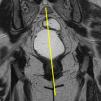

Las secuencias FSE T2 son útiles para evaluar posibles alteraciones musculares, como adelgazamiento o desgarros, en especial del músculo puborrectal (fig. 5). La serie axial debe planificarse en paralelo al propio puborrectal (línea H), desde el ano hasta un nivel superior al sigma. La serie coronal debe planificarse en perpendicular al puborrectal, desde la sínfisis púbica hasta el coxis (fig. 6).

Las secuencias dinámicas FIESTA se componen de múltiples imágenes de un mismo plano (multifase), obtenidas principalmente durante la realización de esfuerzos y cuya posterior visualización en sucesión rápida muestra el movimiento del contenido pélvico. Este tipo de secuencia permite obtener imágenes nítidas de las estructuras en movimiento, ya que cada imagen se obtiene en décimas de segundo (emplear la opción array spacial sensivity encoding technique [ASSET] contribuye a acelerar la adquisición). En nuestro protocolo obtenemos una serie coronal de 50 imágenes durante maniobra de Valsalva planificada sobre el canal rectal, útil para observar posibles rectoceles laterales (fig. 7). Obtenemos asimismo varias series de 120 imágenes de un plano sagital medio de la pelvis, centrado sobre el eje largo del canal rectal y cortando el cérvix (fig. 8). Es importante mantener esta orientación —salvo que el cérvix se encuentre desplazado lateralmente en exceso— para que este no quede fuera de plano y pueda visualizarse correctamente un posible descenso. Esta serie se realiza 4 veces: en reposo, con maniobra de contención, en maniobra de Valsalva y mientras el paciente tose. Finalmente, durante la evacuación, obtenemos una serie similar con 250 imágenes. Al tratarse de maniobras que conllevan presión abdominal, pretende observarse la respuesta del contenido pélvico ante tal presión. La serie adquirida durante la evacuación muestra además la función del músculo puborrectal, el recto y el canal anal. Si se produce una evacuación incompleta, es conveniente realizar una segunda serie. En el caso de las mujeres, puede valorarse si es necesario que la paciente realice una digitación intravaginal para favorecer la evacuación definitiva.